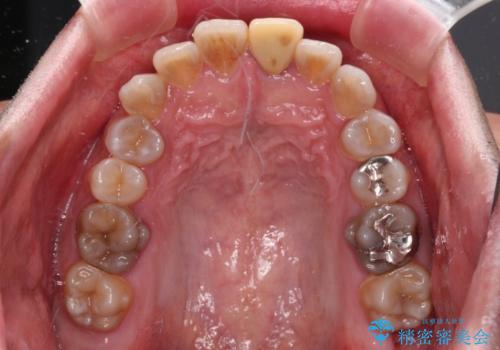

- 飛び出した前歯を気にして来院された患者様です。

口元を引っ込めるために上下左右の第一小臼歯4本を抜歯することとしました。

特徴的な歯の色が気になっているとのことで、今後セラミッククラウンによる審美歯科治療を検討されているとのことで、矯正治療の後戻りが落ち着いたタイミングで治療を進めていく予定です。